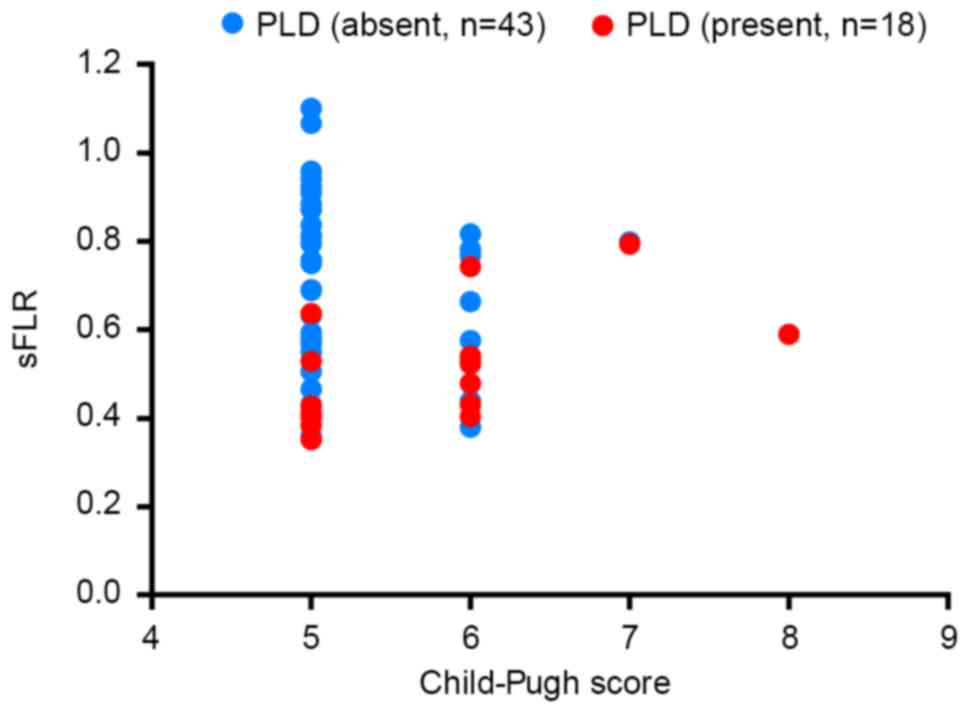

sFLR and CPS are linked to postoperative liver

dysfunction. The distribution of PLD in patients with different

CPSs and different sFLRs is demonstrated in Fig. 4. According to the distribution of PLD,

the majority of patients with a CPS of 5 who developed PLD had an

sFLR of <43%, and the majority of the patients with a CPS of 6

who developed PLD had an sFLR of <54%.

outcomes (25,26). Theoretically, with a higher CPS, a

larger FLR is required to avoid PLD. Judging from the distribution

of PLD (Fig. 4), data from the

present study revealed that to avoid PLD in HBV-related HCC

patients following hepatic resection, an sFLR of 43% is relatively

safe when the CPS is 5, and an sFLR of 54% is relatively safe when

the CPS is 6. It is predicted that a higher sFLR is required when

the CPS is 7 or 8. These results require testing and verifying with

more cases in clinical practice, in particular with more patients

with a CPS of 7 or 8.